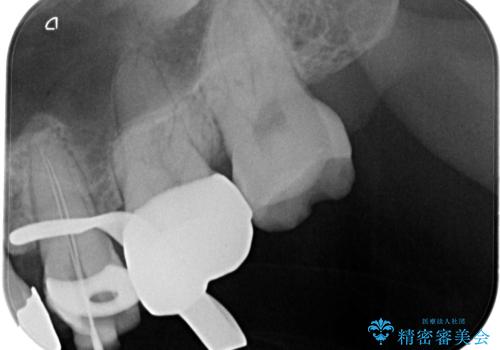

術前に神経の部分壊死と診断しましたが、神経をあけたときに出血が一切無かったので神経が死んでいるという診断は正しかったという事になります。

神経の処置にはマイクロスコープを使用しながら唾液を根管内に入れないようにラバーダムシートを使用しながら治療を行っています。